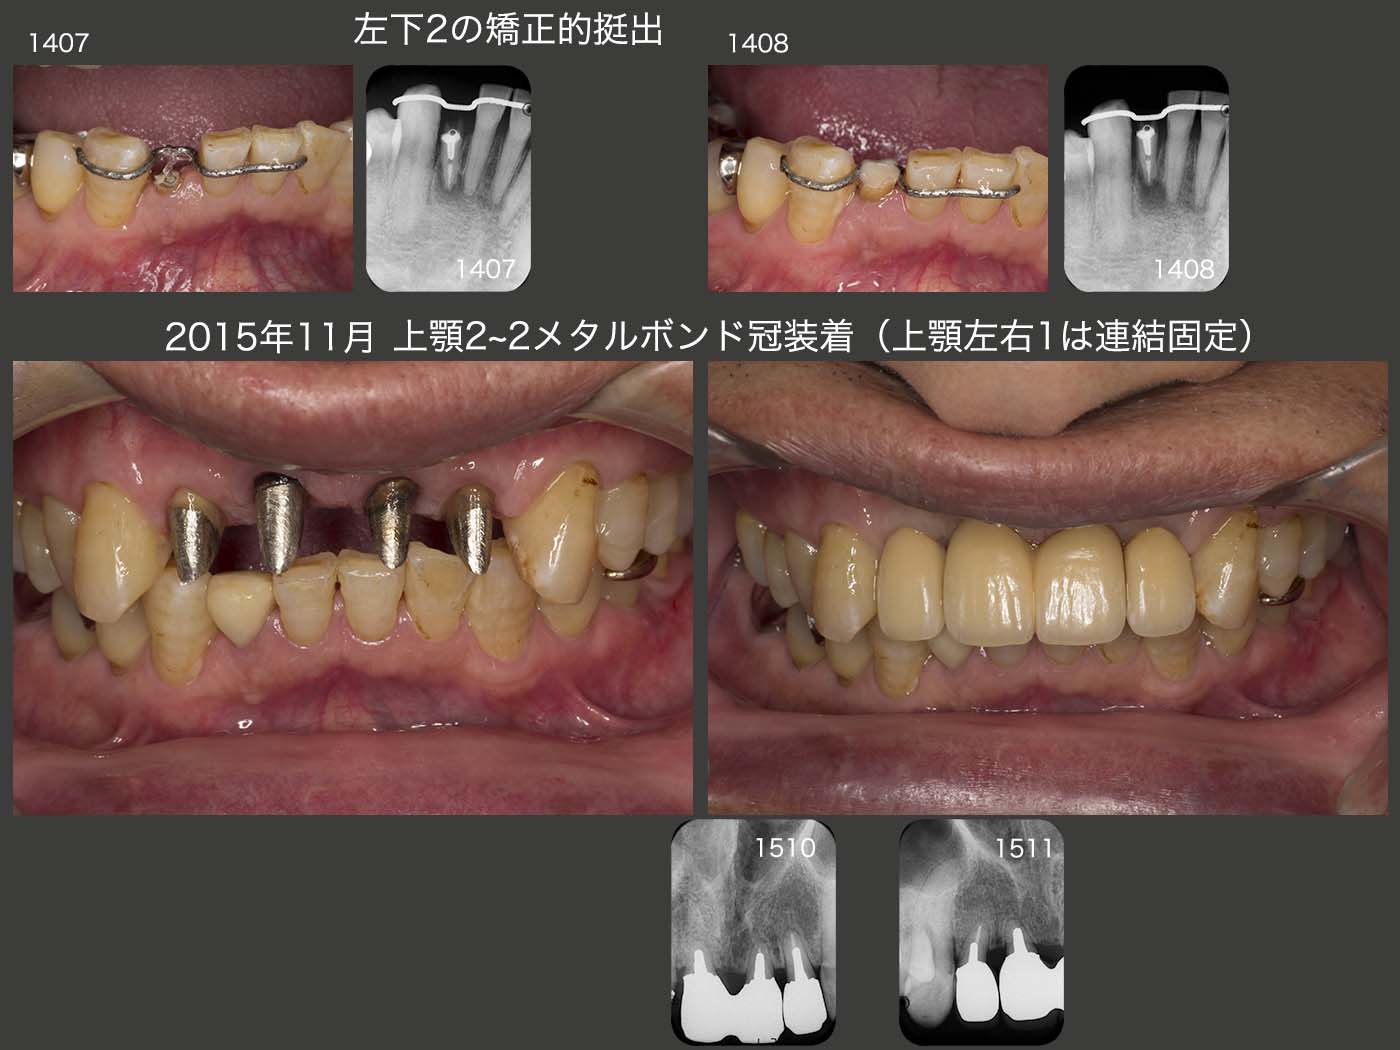

2013年10月25日に,まず上顎左右側切歯の矯正的挻出を開始し,12月20日に終了した.14年1月22日に上顎2〜2の歯冠長延長術を行った.ここで,両側側切歯にコアを植立し,暫間被覆冠が外れにくくした.また,両側中切歯にもピッグテールが掛けられるようになったので,2月24日から中切歯の矯正的挻出を開始し,3月17日に終了した.3月29日に両側中切歯の歯冠長延長術を再度行い,歯肉縁上歯質を確保した.患者さんは,2から2の単独植立を希望された.しかし,両側中切歯の動揺が大きかったので,同部は連結固定することにし,一方両側側切歯の動揺は僅かであったので,単独植立することにした.ただ,前歯は審美優先で,ここで物を食いちぎることはできないし,絶対にしてはいけないと,来院のたびに力説した.

右下2も同様に矯正的挻出および歯冠長延長術を行い,保存した.

上顎2〜2は,2014年6月に両側中切歯にコアおよび暫間被覆冠装着し,1年5ヵ月間経過を観察した後の15年11月にメタルボンド冠を装着し,ここで初診終了とした.なお,この期間中に他部位の治療(15年8月,左下の可撤式ブリッジ装着)も行っていた.